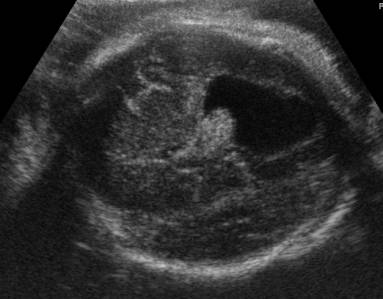

Colpocephaly |

Colpocephaly (dilatation of the occipital horn of the

lateral ventricle). |

o

Enlarged

occipital horns (colpocephaly) of the lateral ventricles,